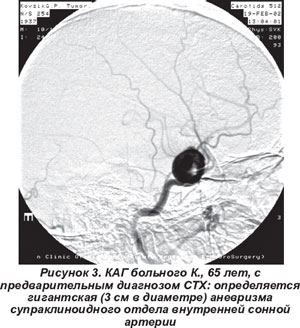

Сосудистые мальформации чаще встречались у женщин (70,5 %), почти всегда на фоне декомпенсации артериальной гипертензии. Преобладал острый характер процесса и умеренный болевой синдром. Глазодвигательный и отводящий нервы вовлекались в процесс одинаково часто. Экзофтальм и хемоз практически не встречались. При МРТ и КАГ у 13 пациентов выявлены артериальные аневризмы (3-30 мм в диаметре) супраклиноидного отдела внутренней сонной артерии (рис. 3); в 2 случаях - в инфраклиноидном отделе; у 2 больных - каротидно-кавернозные соустья. В 1 случае в каротидном бассейне одновременно обнаружено две аневризмы. У 7 пациентов наблюдали разрывы аневризм и в СМЖ определяли эритроциты. В 3 случаях при МРТ в динамике отмечали спонтанное тромбирование аневризм. Уровни интерлейкина-6 и ФНО-альфа в сыворотке крови и СМЖ не изменялись. У 6 больных проведена операция клипирования шейки аневризмы.